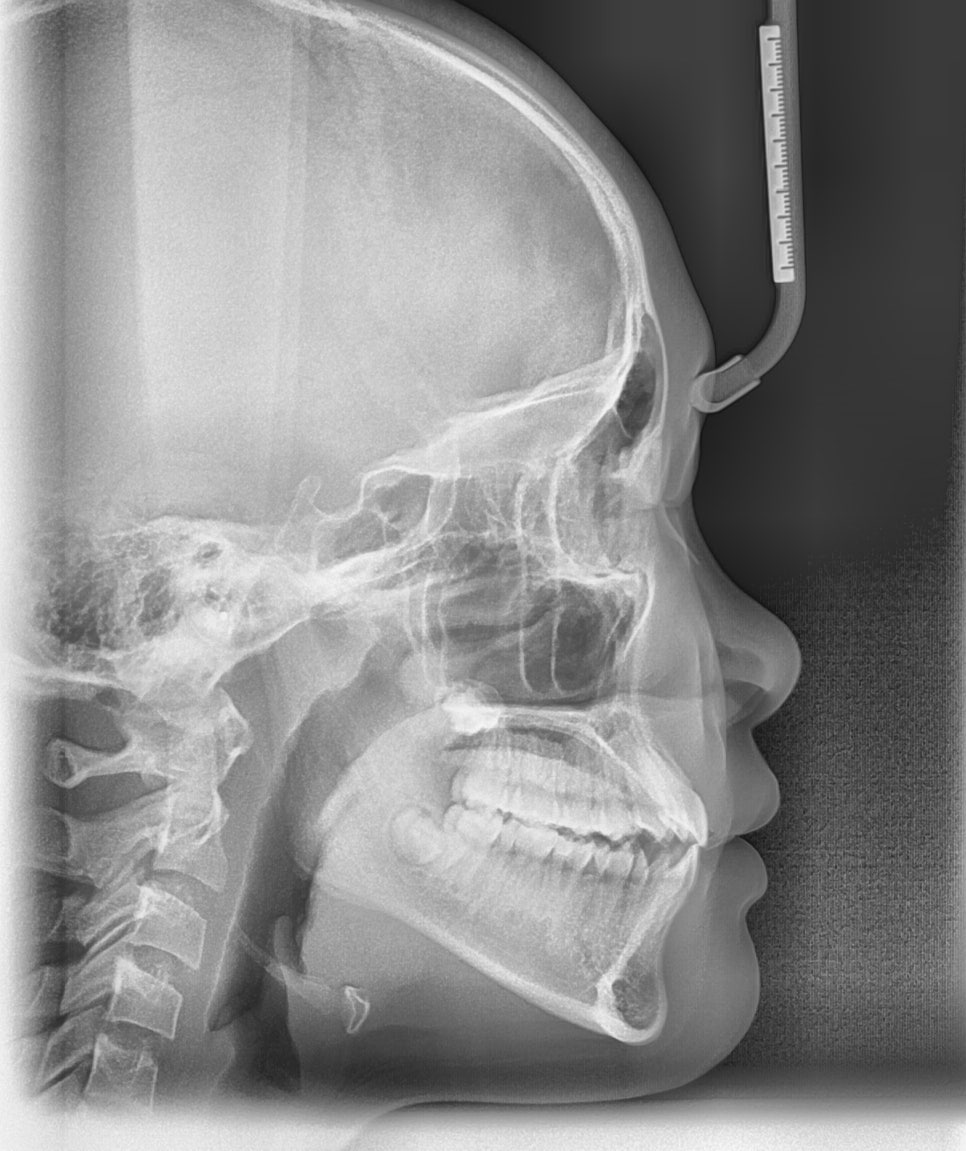

초진시 위아래 앞니끼리 맞물리는 절단교합 양상을 보이고 있었으며 아래 앞니는 치아 사이가 많이 벌어져 있었습니다. Cephalometric x-ray 상 아래턱이 발달한 제 3급 부정교합 (주걱턱) 양상을 보이고 있었고, 수완부사진 성장판 검사 결과 SMI 7~8단계에 해당하여 사춘기 최대 성장기는 지난 상태였습니다.

Cephalometric X-ray